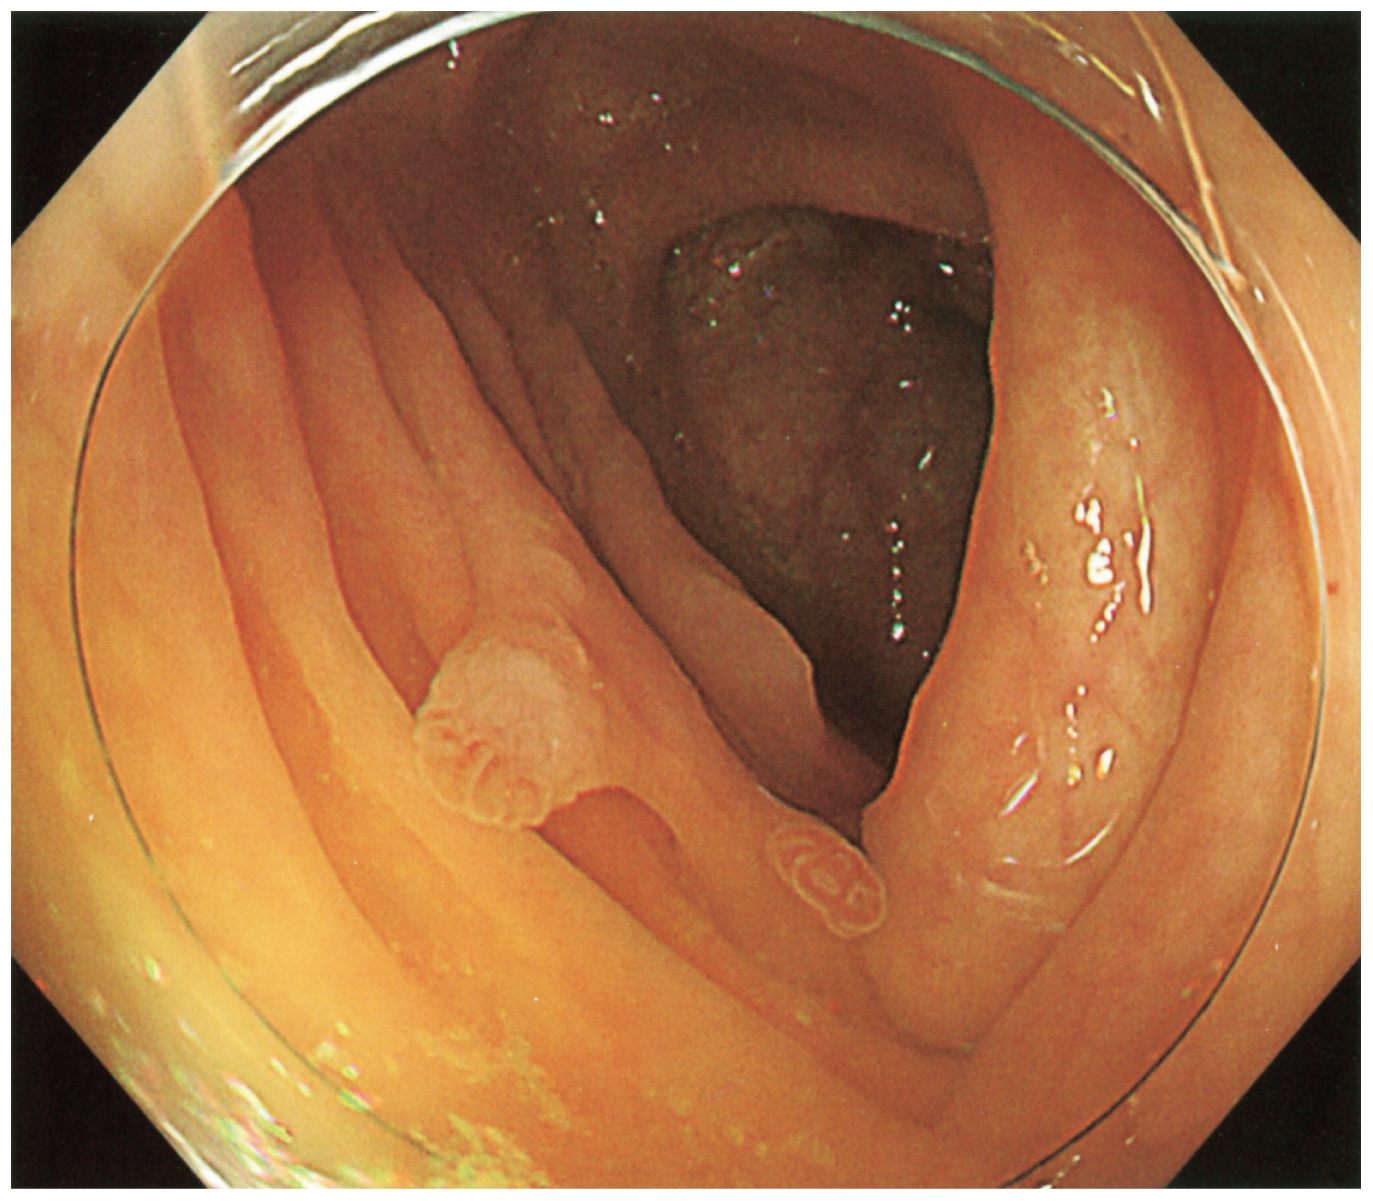

4歳の女児。口唇,口腔内の色素斑を主訴に母親に連れられて来院した。3歳ごろから口唇,口腔内に黒い色素斑が出現し,徐々に増加してきたため母が不安になり受診した。兄弟姉妹はいない。母と母方の祖父に複数のポリープを大腸に認め,治療歴がある。成長や発達に異常は認めない。口唇,口腔内に径1~5mmの黒い色素斑を認める。患児の下部消化管内視鏡検査の下行結腸像を下に示す。